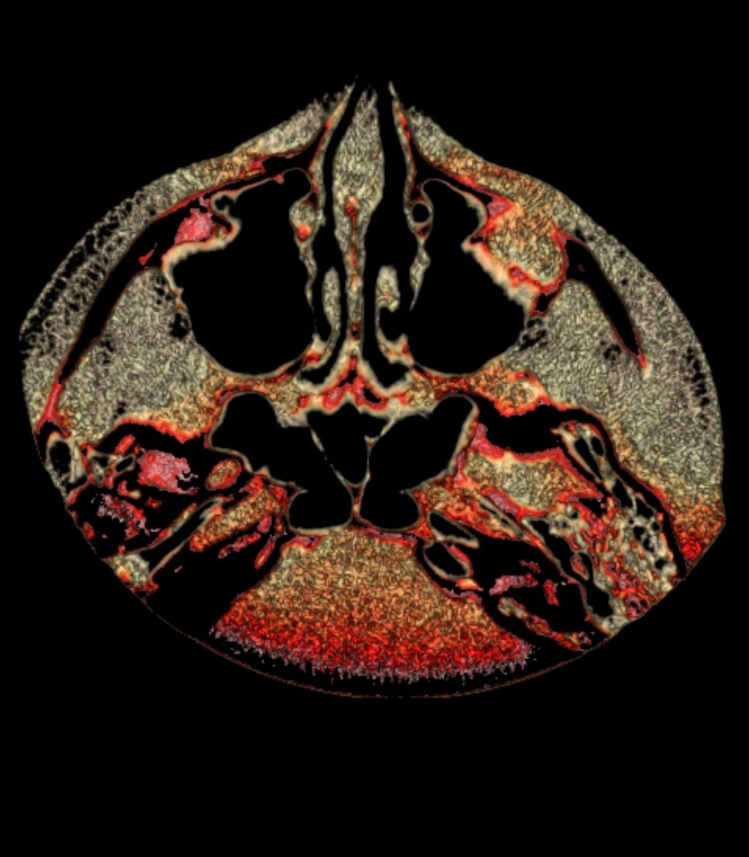

TC de face (do Hióide à Glabela), reconstrução 3D do tecido ósseo, radiografia panorâmica, telerradiografia lateral com traçado, cortes transversais e axial de maxila e mandíbula e arquivo DICOM- entregue em pasta de Pvc.

TC de face (do Hióide à Glabela), reconstrução 3D do tecido ósseo, radiografia panorâmica, telerradiografia lateral e frontal com traçado, cortes transversais e axial de maxila/mandíbula e arquivo DICOM – entregue em pasta de Pvc.

TC de face (do Hióide à Glabela), reconstruções 3D do tecido mole/ósseo/vias aéreas, radiografia panorâmica, telerradiografia lateral e frontal com traçado, cortes transversais e axial de maxila/mandíbula, ATM e arquivo DICOM – entregue em pasta e caixa de Pvc.